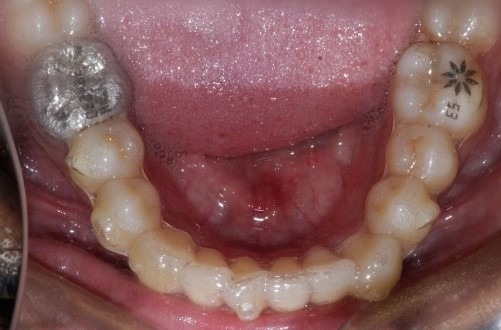

Before: Lower

During The Treatment